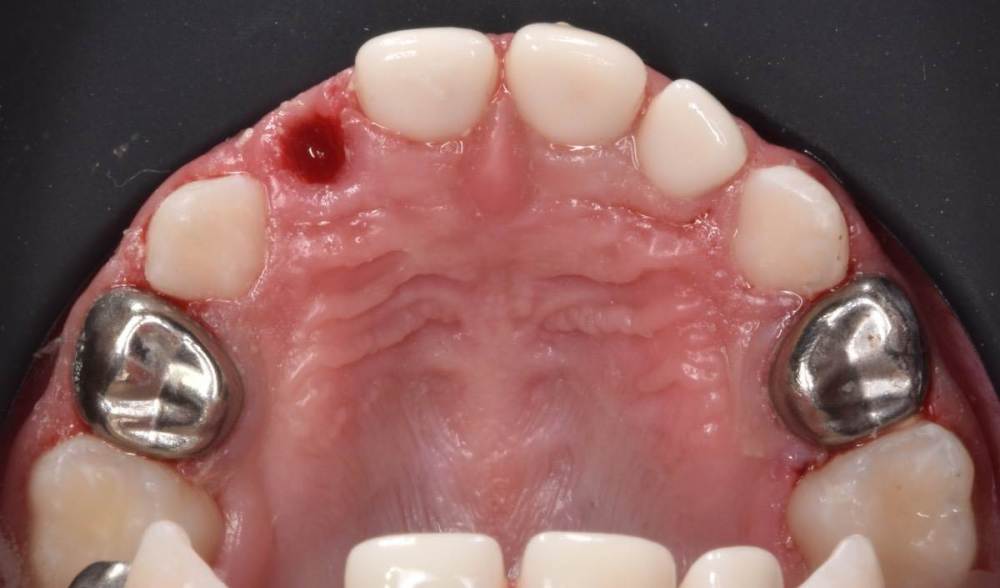

CRAZYDUCK Опубликовано 28 июня, 2022 Автор Поделиться Опубликовано 28 июня, 2022 Ладно , только по снимку нельзя установить диагноз . нет в 6.5 кариозных полостей . только нерентгенконтрастная пломба из градиа , которую я поставила двумя годами ранее . Вот оно как было ДО 3 1 Ссылка на комментарий